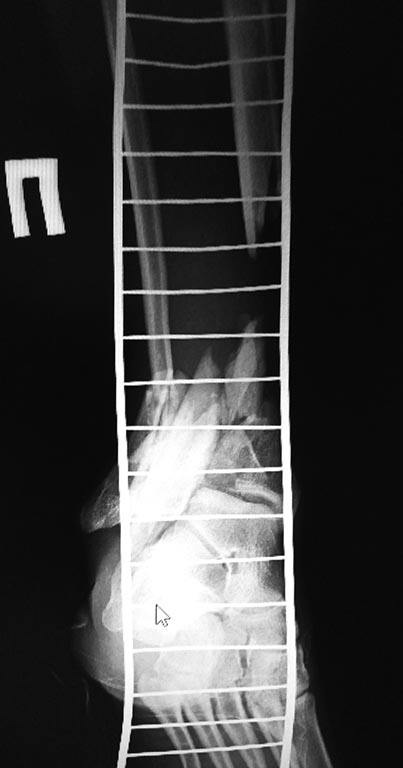

1 вариант, учитывая скомпроментированную суставную поверхность

б/берцовой кости, выполнить ретроградно  штифтом  артодез с фиксацией

перелома б/берцовой кости. Выполнить рассверливание и открыто не

вмешиваться.

2 вариант)  микрохирурги предлагают открыться на место перелома

б/берцовой кости, удалить нежизнеспособную кость и выполнить

трансплантацию м/берцовой кости с другой голени ,  на сосудистой ножке.